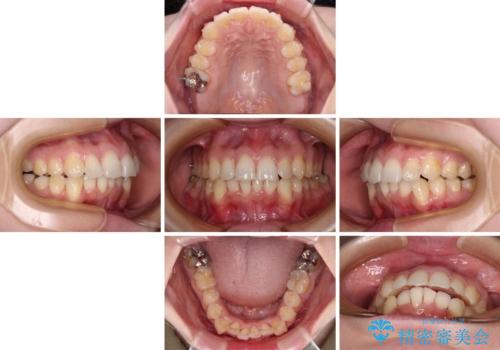

- 前歯のデコボコで前方に出ていることを気にして来院された患者様です。

上顎前歯が捻れて前方に飛び出しており、下顎前歯もそれに沿うようにデコボコとなっていました。

IPR(歯と歯の間を削る処置)によりスペースを獲得して上下顎前歯のデコボコを改善し、飛び出している前歯が引っ込むように設定し、インビザラインにて矯正治療を行うこととしました。